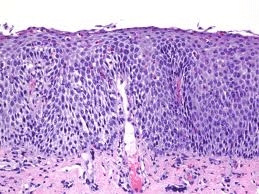

Eosinophilic esophagitis, also known as EE or EoE, is an allergic inflammatory disease and typically chronic disorder that affects from one to four of every 10,000 people in the United States. It is a recently recognized disease with increasing diagnoses, resulting in part from growing awareness of the condition. An estimated 50 percent of patients with eosinophilic esophagitis also have seasonal allergies or asthma. Many others also have food allergies or eczema. Some patients note a seasonal flare up of the condition, typically in the spring and in the summer.